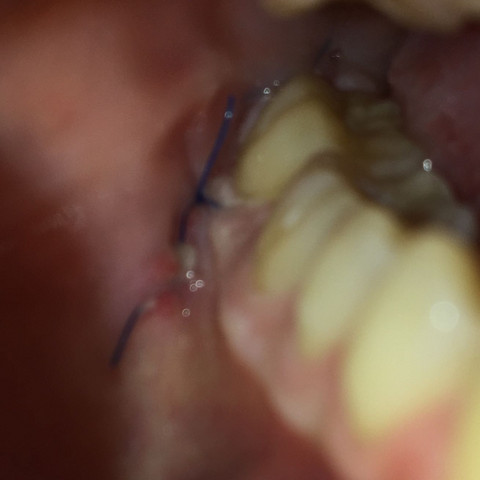

Nach Weisheitszahn Op Rot Am Faden Gesundheit Und Medizin Zahne Zahnarzt

Aufgerissene Und Ungenahte Wunde Nach Weisheitszahn Op Schmerzen Blut Operation